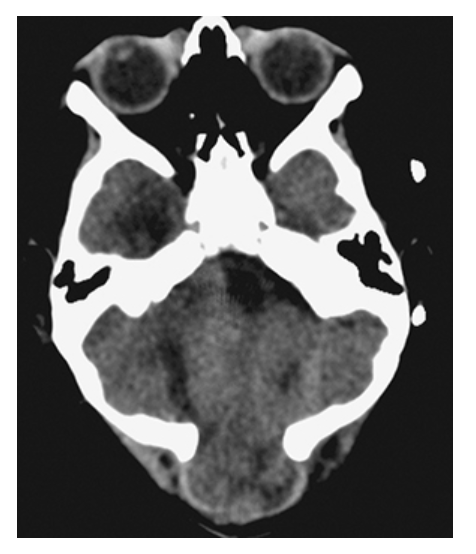

Dandy-Walker Syndrome. Axial NECT shows a large posterior fossa with a CSF density cyst, hypoplastic cerebellar hemispheres, and absence of the vermis.

Dandy-Walker Syndrome. Sagittal T1W image shows a massively dilated fourth ventricle, expanded posterior fossa, high-riding torcula, and hypoplastic cerebellum.

What is A

Dandy-Walker Syndrome. Axial T2W and coronal T1W

What is B

Dandy-Walker Syndrome. Axial T2W show absence of the cerebellar vermis.